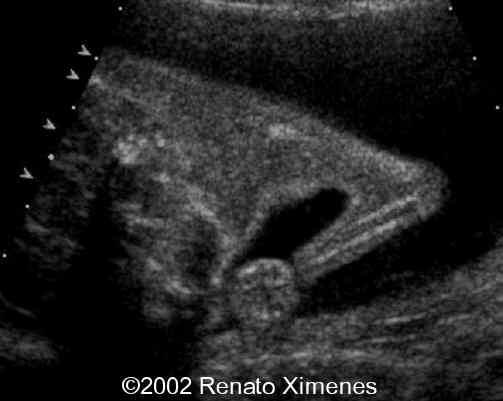

The cystic hygroma extends down the back of the fetus and pleural effusions are visible:

case0072-3

case0072-4

case0072-5